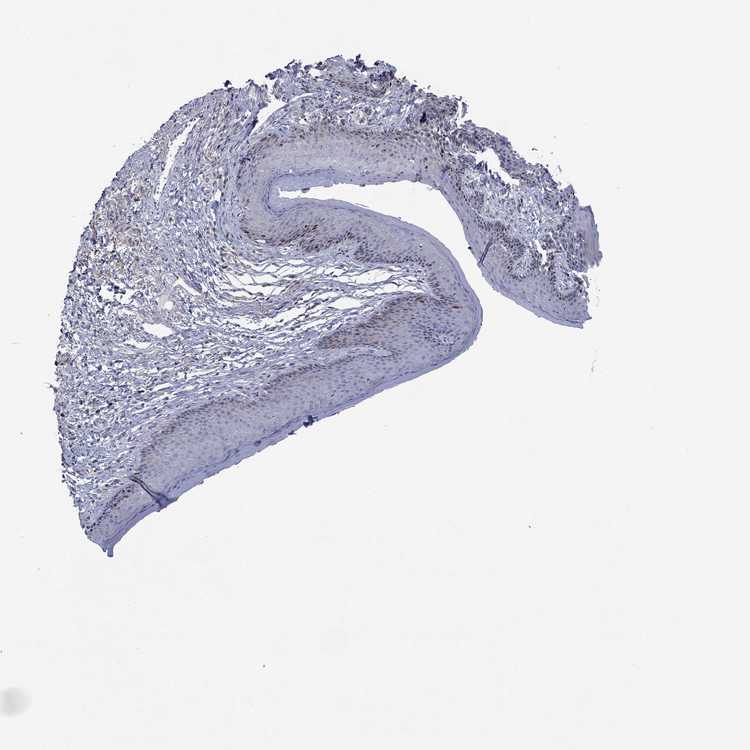

SKIN 1 - Antibody stainingi

Antibody staining in the annotated cell types in the current human tissue is reported as not detected, low, medium, or high, based on conventional immunohistochemistry profiling in selected tissues. This score is based on the combination of the staining intensity and fraction of stained cells.

Each image is clickable and will lead to virtual microscopy that enables deeper exploration of all samples and also displays staining intensity scores, fraction scores and subcellular localization as well as patient and tissue information for each sample.

Antibody HPA078816

Langerhans Not detected

Fibroblasts Not detected

Keratinocytes Not detected

Melanocytes Not detected